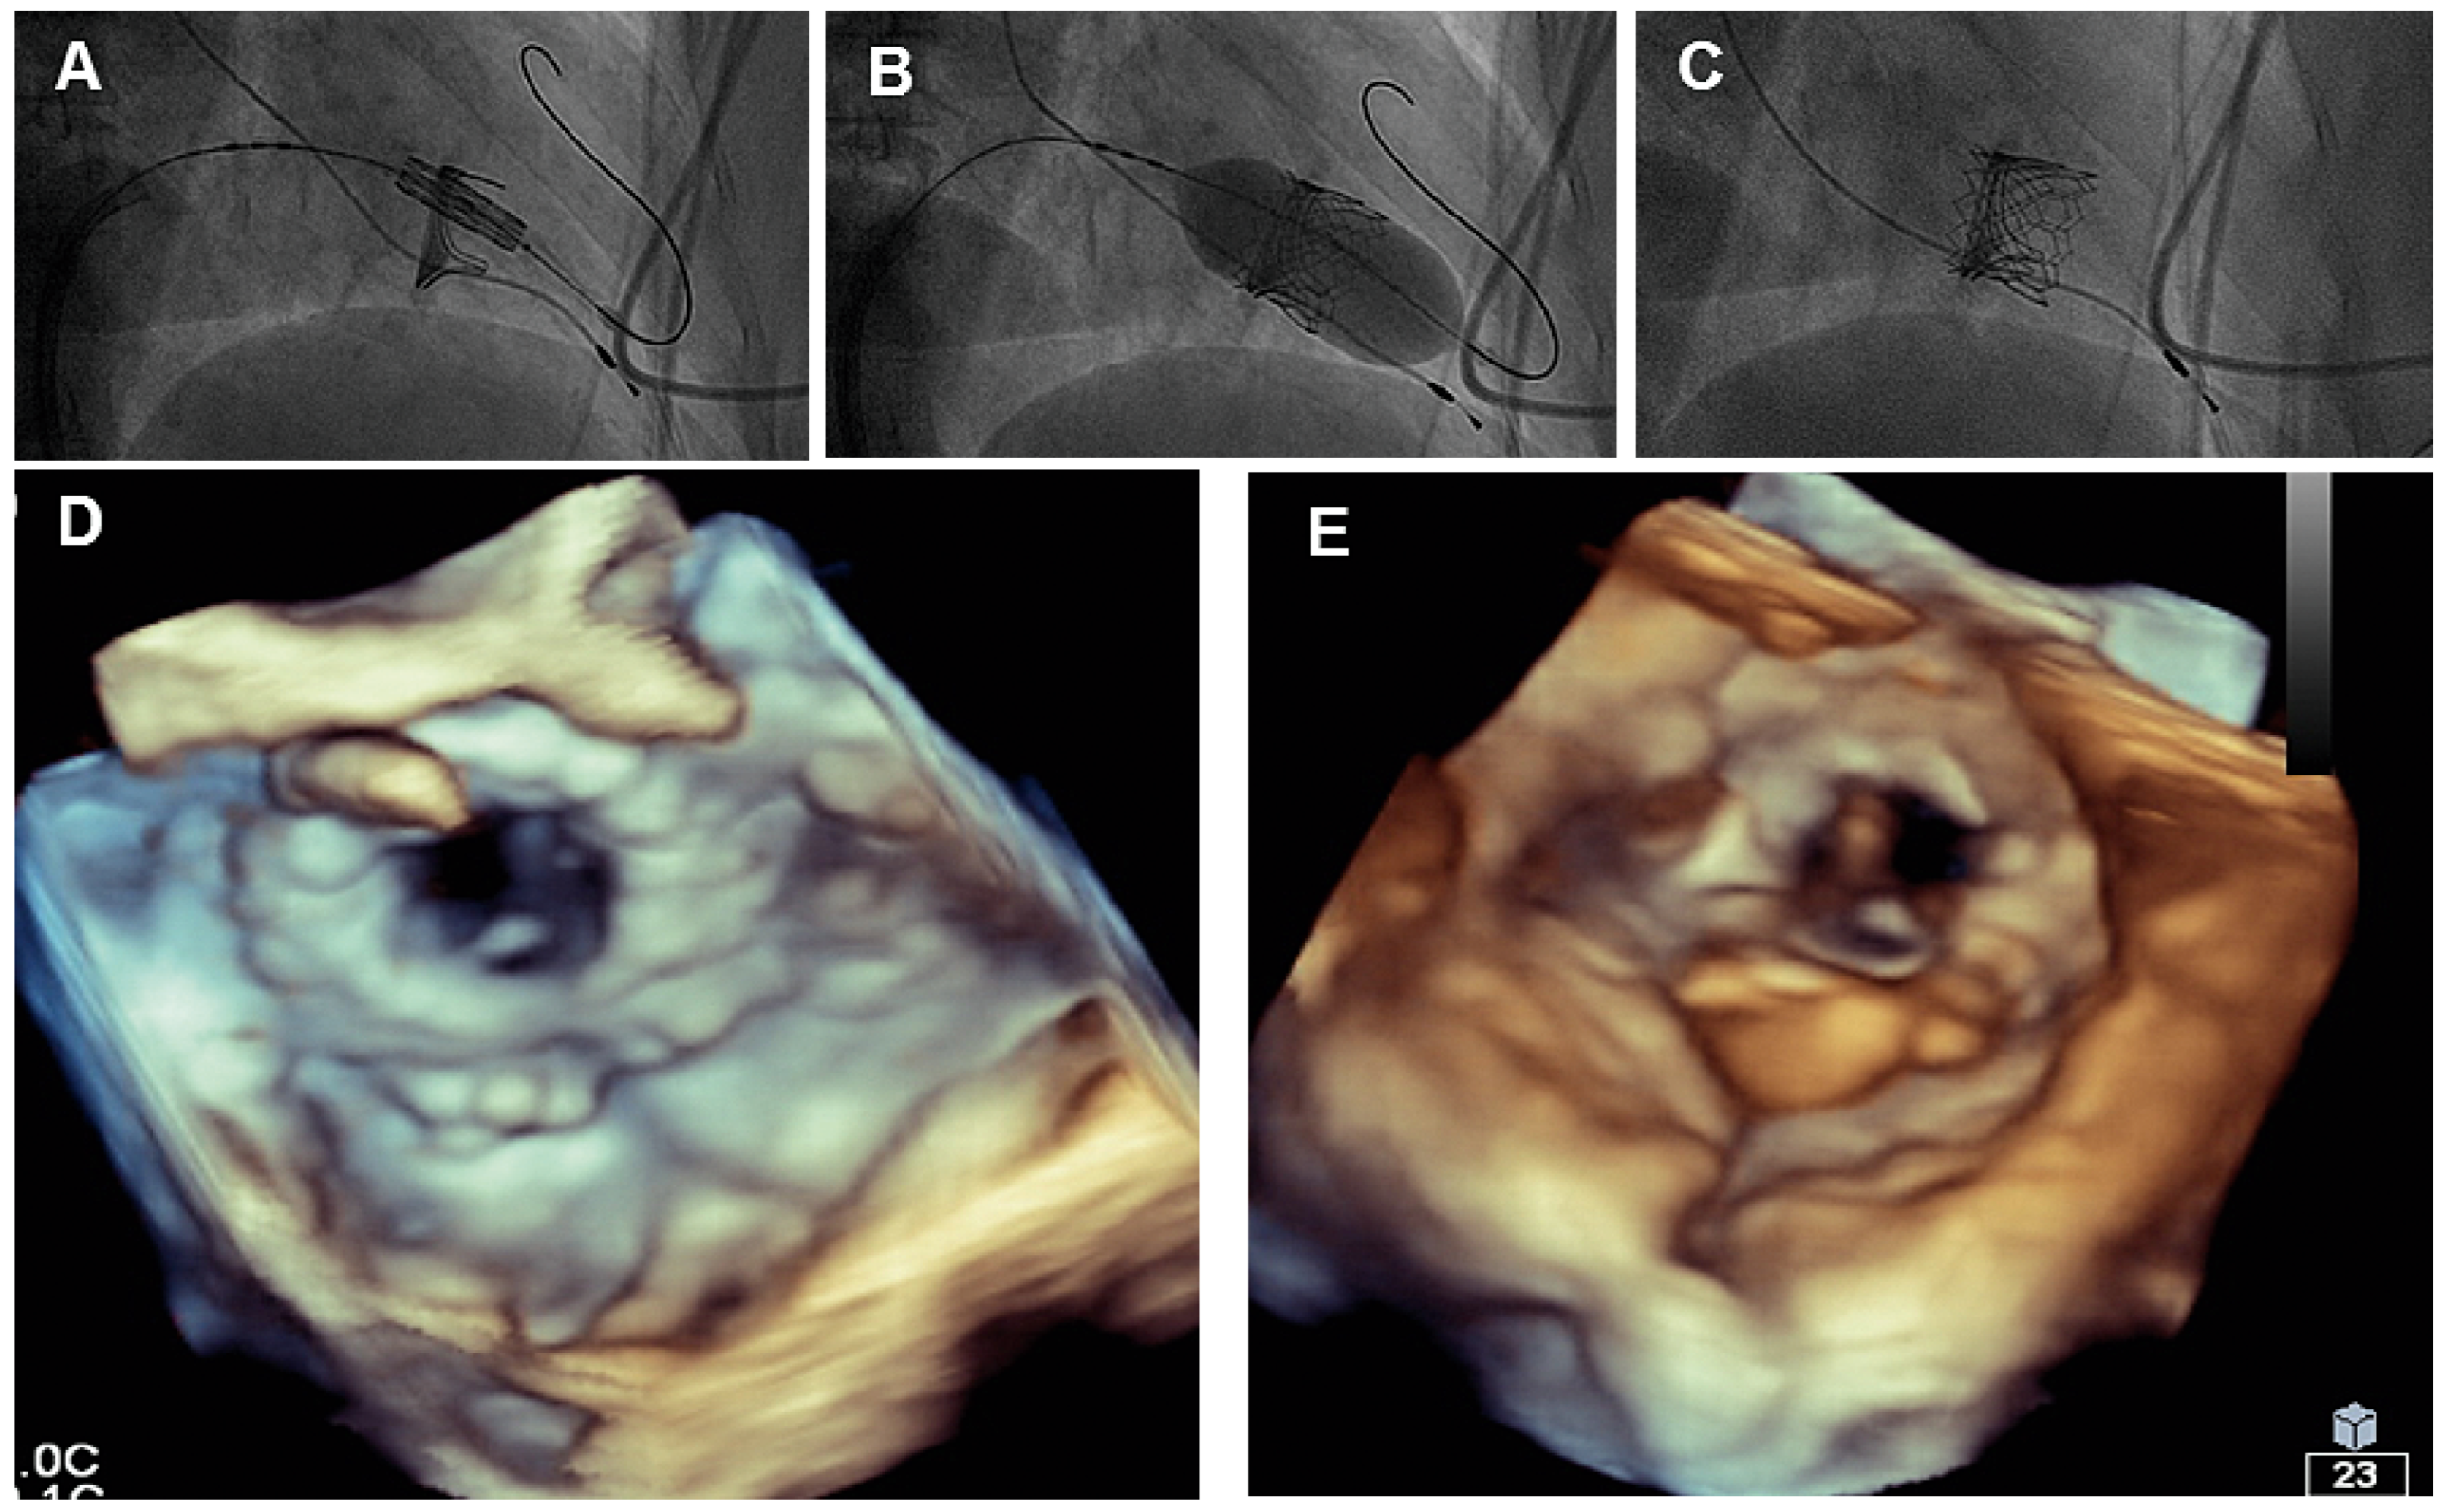

Caval valve implantation